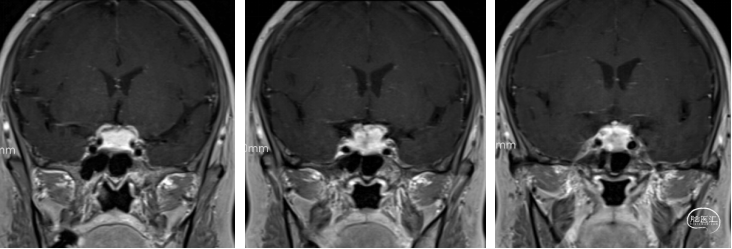

术后核磁:肿瘤切除干净,垂体及垂体柄保留完好,术区无出血。

术后复查核磁肿瘤切除干净,右眼视力情况较前改善。术后患者出现轻度尿崩,低钠,皮质醇及甲状腺素水平降低,予以对症治疗后好转。

术后视力视野检查(2025年3月31日):左眼视力:指数/50cm,VFI:0%。右眼视力0.4,VFI:21%。

近期视力视野检查(2025年5月15日):左眼视力:指数/50cm,VFI:0%。右眼视力0.4,VFI:37%。患者双眼视力同前,右眼视野较前显著改善。